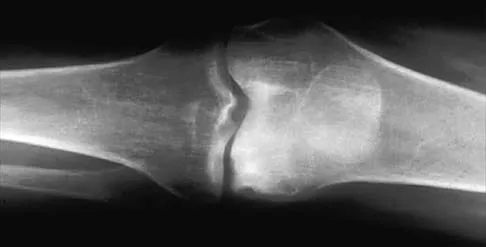

A 35-year-old man has atraumatic painless limited elbow motion. Radiographs are shown in Figures 33a and 33b. What is the most likely diagnosis?

Based on the radiographic findings, the patient has melorheostosis, a rare, benign connective tissue disorder that is characterized by a cortical thickening of bone. It produces a "dripping candle wax" appearance with dense hyperostosis that flows along the cortex. Ectopic bone formation is a consideration but is associated with injuries or burns. Bone infarcts produce intraosseous sclerosis typically affecting the distal femur with the "smoke up chimney" appearance. Infection is always a consideration but typically does not have the linear osteitis seen in melorheostosis. Juxacortical chondroma is a benign cartilage growth that arises from the capsule and may involve the underlying cortical bone but rarely the medullary canal. Campbell CJ, Papademetriou T, Bonfiglio M: Melorheostosis: A report of the clinical, roentgenographic, and pathological findings in fourteen cases. J Bone Joint Surg Am 1968;50:1281-1304.